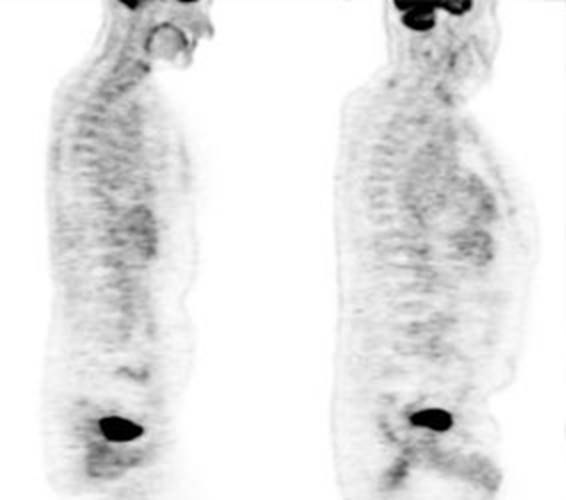

Figure 21 - Marrow activity: The images below are from

two separate patients each showing mild FDG accumulation within the vertebral

bodies.